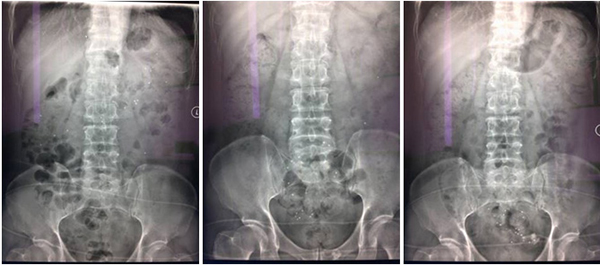

2、结肠传输试验

结肠传输试验是检查人体结肠传输功能的一种方法。通过口服不透X光标记物,使其混合于肠内容物中,在比较接近生理条件的前提下,分别于口服标记物后24小时、48小时及72小时摄片,观察结肠的运动情况.

结肠传输试验阴性

结肠传输试验阳性

结肠传输试验阳性 (考虑出口梗阻型)